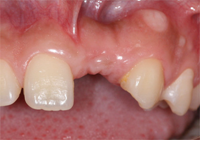

![]() |

| Mất 1 răng |

Dựa trên phim Panorama ta có thể thấy R24 bị tiêu xương ổ răng do mất răng lâu ngày

Kế hoạch điều trị: cấy 1 implant nâng đỡ R24, ghép xương